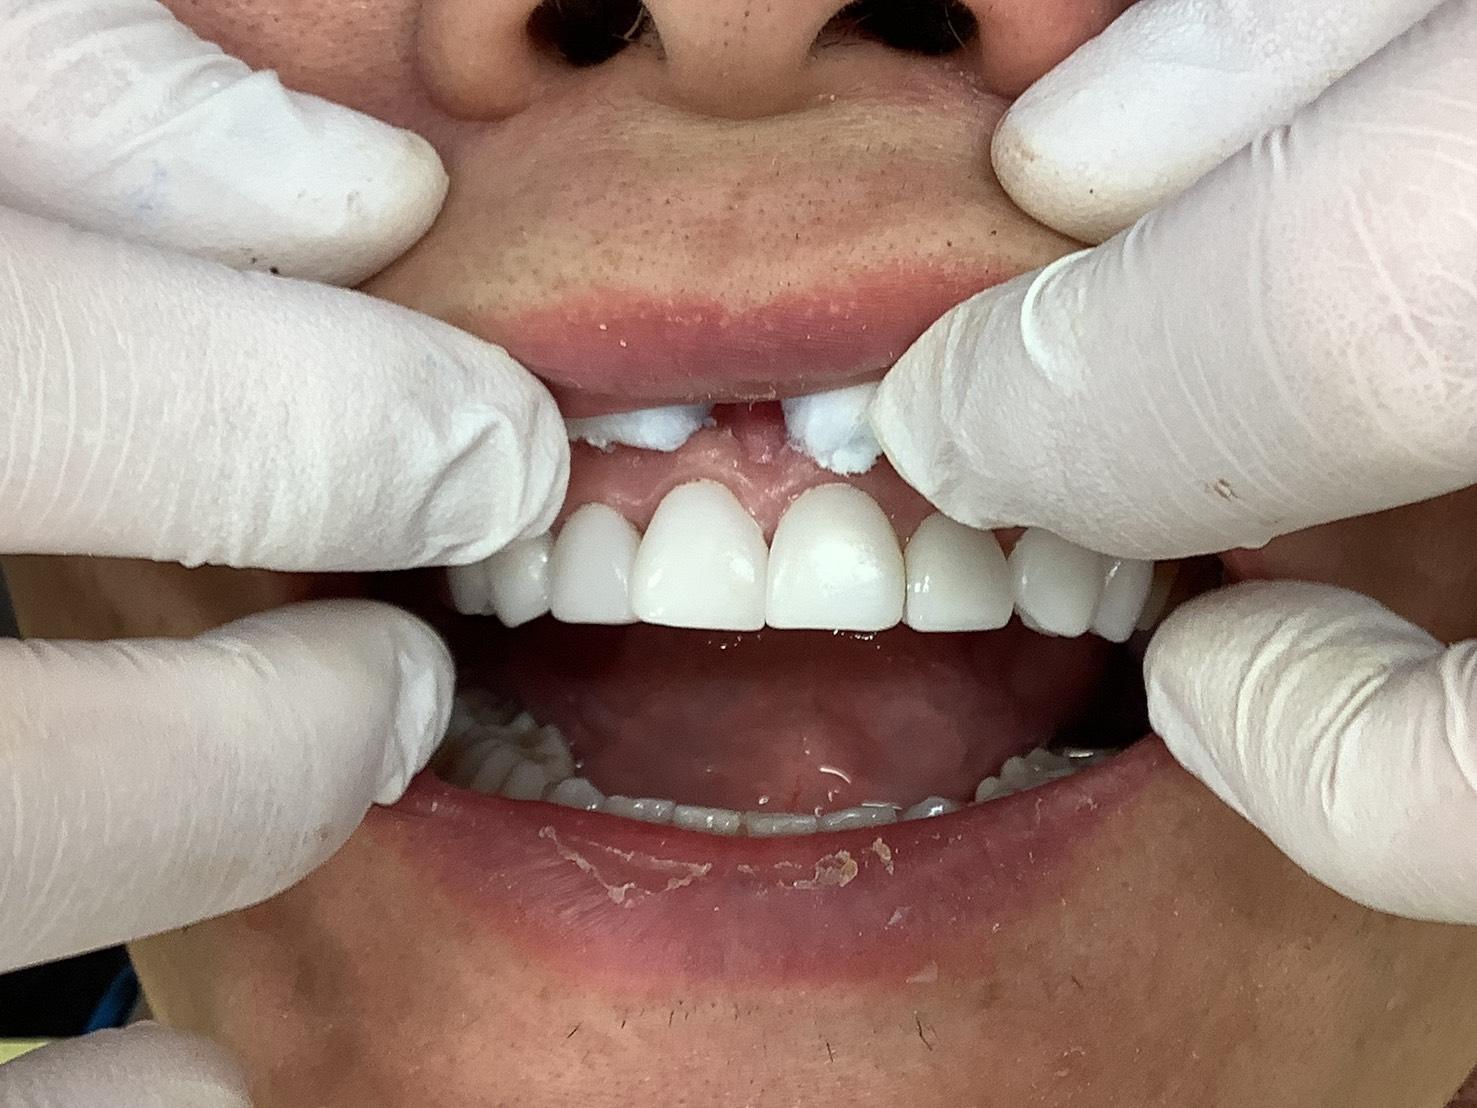

CASE 12

BEFORE

▶

AFTER

30代女性。「ホワイトニングでは満足できる白さにならない」「歯の形や隙間をきれいに整えたい」というご希望で来院。一番の懸念点は「健康な歯を削ること」だったため、ご自身の歯をほとんど削らずに施術できるエンジェルべニアを選択されました。